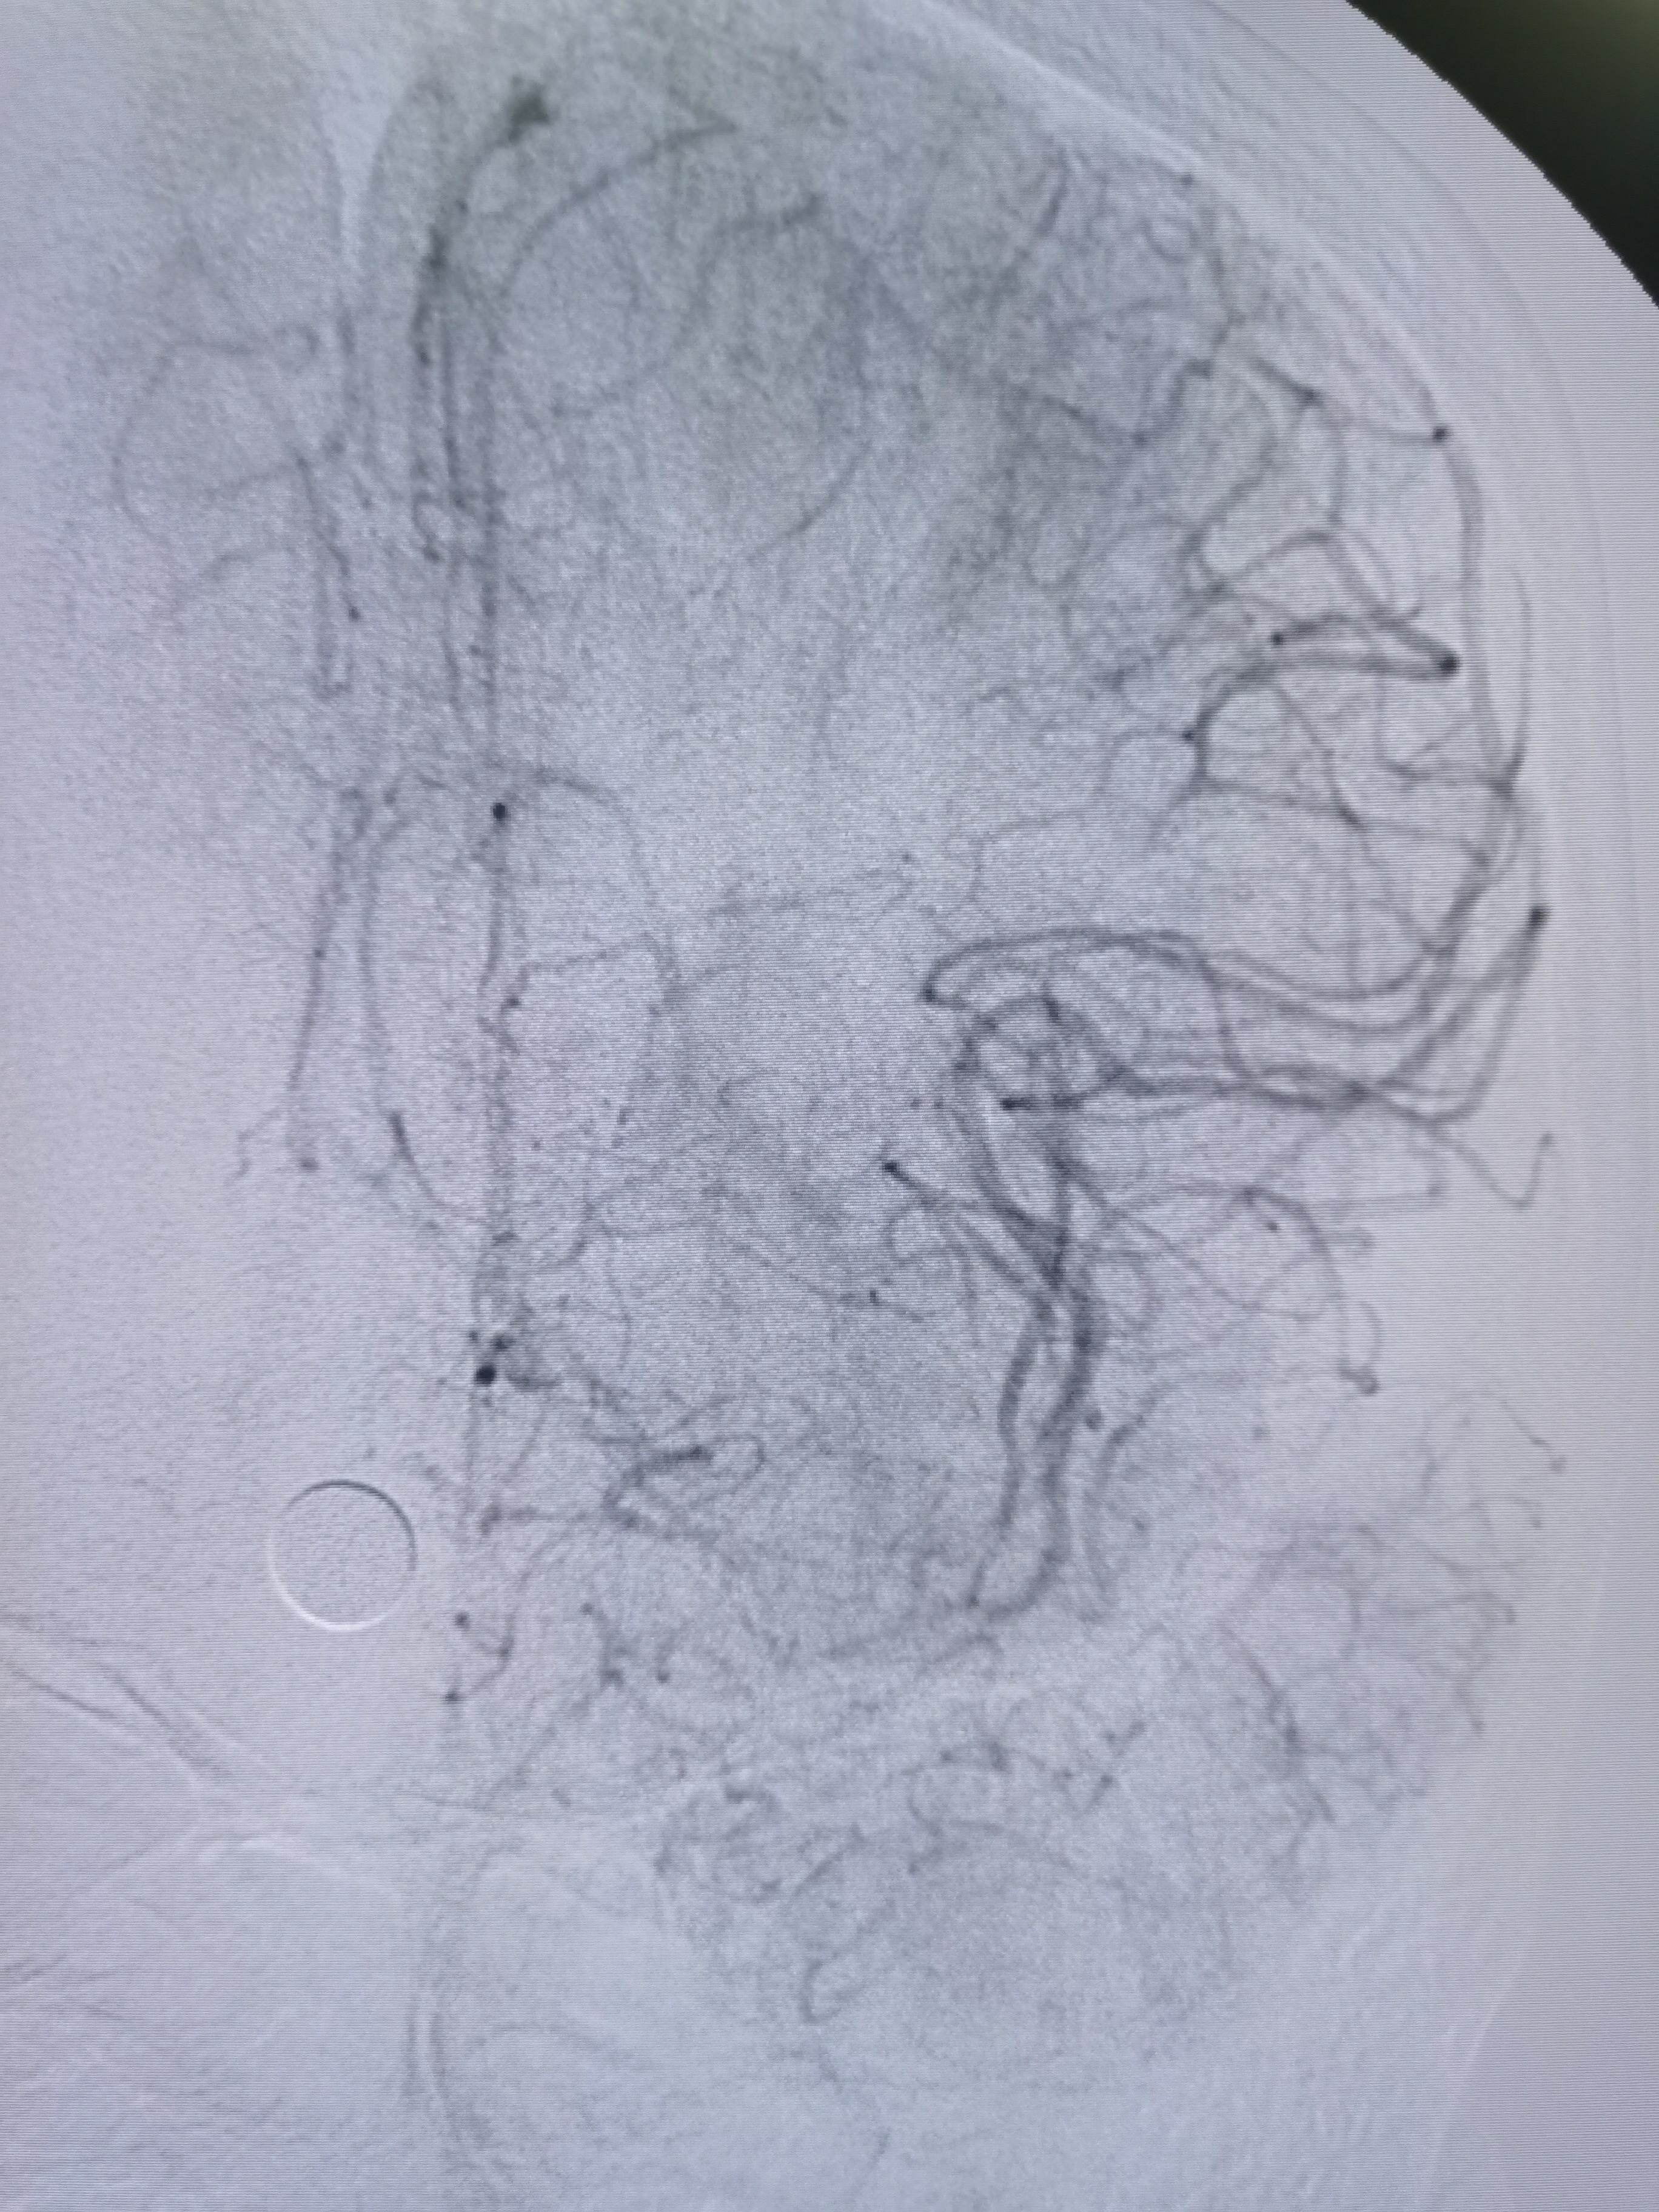

全麻后,将8F导引导管及中间导管顺利到位,建立路径,在路径图下微导丝携微导管顺利通过病变。

微导管确认位于真腔,交换入Transend300导丝。

2.0/15球囊扩张闭塞处。

扩张后造影见近端显影,远端血管仍闭塞。

将球囊前送,再次加压扩张。

扩张后造影见血管再通,血流通畅。

侧位造影见血流通畅。

观察15分钟后造影血流通畅,未见夹层及明显弹性回缩。

复查造影见颅内狭窄解除,血流通畅,遂未再植入支架,撤出导丝及各级系统,结束手术。患者麻醉苏醒顺利,无新发神经系统症状,给予替罗非班持续泵入,监测生命体征,控制血压避免再灌注损伤。